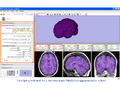

• Update #1: We have successfully compiled the skull stripping algorithm, Simple Paradigm for Extra-Cranial Tissue Removal (SPECTRE) as a Slicer3.4 plugin. The following images show an OASIS brain skull-stripped with the plugin. The method requires a registration. The Affine Registration module of Slicer3.4 does not provide the desired result. Therefore, we will include Deformable BSpline registration and provide a plugin.